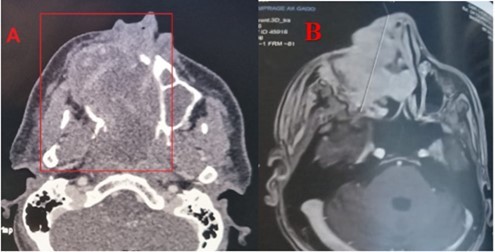

Patient aged 40 years without any surgical medical history who consults at our level in 2022 for a right epistaxis of average abundance with nasal obstruction and an induration next to the maxillary sinus right to palpation. Endoscopy revealed a reddish polypoid mass filling the right nasal cavity without palpable cervical adenopathies, CT returned in favor of an expansive tissue process of the right maxillary sinus, extended to the soft parts and the homolateral nasal cavity. The complete resection of the mass was performed by endonasal surgery (endoscopic maxilectomy). The histological examination found hemangioendothelioma without signs of malignancy with infiltrated margins, external complementary radiotherapy was indicated (50 Gy, 2Gy per day for 5 days a week on the maxillary sinus), a radiological check (MRI) 4 months later does not find any residual tumor. After an absence of 15 months, the patient revisits for resumption of symptomatology with right epistaxis of great abundance requiring 2 globular units, a reddish mass protruding from the nasal vestibule, lysing the bony palate with extension towards the cheek (Figure 1) and alteration of the CT and MRI find an expansive tumor process centered on the nasal cavity and maxillary sinus right of 103x 58 x41 vs 156x67x95mm with currently highly elevated spans, the process is globally hypodense and weakly elevated, presence of some vessels as well as hypervascular portions of peripheral localization at the extended jugal level and in front of the internal canthus, bone palace lysis, with a negative extension balance (Figure 2).

Figure 2.CT scan with PC injection (A) and MRI in axial sections (B) showing the lesion of the right maxillary sinus extended to neighboring structures

CT scan with PC injection (A) and MRI in axial sections (B) showing the lesion of the right maxillary sinus extended to neighboring structures

Angiosarcoma is a very rare malignant tumour that accounts for about 1 to 2% of all sarcomas 1. Nasosinusial localization is exceptional: 4% of angiosarcomas occur in the pharynx, oral cavity or sinuses 8; only 24 cases have been reported from 1974 to 2009 9. The age range varied between 8 and 81 years, our patient was 40 years old, with a male predominance (16 men for 8women in the 24 cases reported), which was the case with our patient 10. The etiopathogenesis of angiosarcomas is not known, radiation exposure presents a risk up to seven times greater for secondary angiosarcoma 9, vinyl chloride, arsenic and thorium dioxide, which could cause lymphedema, would cause angiosarcoma 11 in our patient, where there was secondary sarcomatous transformation after irradiation. The clinical presentation of angiosarcoma is generally mild in the initial phase 6. The macroscopic aspect is unspecific 12. It comes in the form of polyps or red or purplish plaques sometimes taking the appearance of a hematoma. This misleading clinical aspect requires follow-up and biopsy at the slightest doubt. Our patient had unilateral nasal obstruction with epistaxis of small abundances and smooth reddish mass in the nasal cavity and, at a later stage, the tumor syndrome becomes evident (epistaxis of great abundance, blocked nose, alteration of the general condition) with extension to surrounding structures (eyeball, palate, skin). The radiological presentation is extremely variable and not very specific. On imaging, the tumour has variable dimensions (ranging from 2 to 8 cm in published cases) with hypervascular lesion, heterogeneous contrast uptake and signs of bone lysis on CT scan, and can be evaluated for its extent. In MRI, the tumour has a low-intensity signal on T1 weighted sequences and a high-intensity heterogeneous signal on T2-weighted sequences with an enhancement of intense and heterogeneous contrast 4. The diagnosis of certainty is established by histopathological staining and confirmed by immunohistochemistry 1, 3. Three microscopic aspects have been described: fusiform cells of the epithelioid type and of the undifferentiated or solid type. In undifferentiated forms, the vascular marker CD31 is useful for diagnosis. Other less specific or sensitive markers may be used (Willebrand factor, CD34, lectins) 9. Epithelioid forms pose the problem of differential diagnosis with poorly differentiated squamous cell carcinomas, especially since there is a strong expression of AE1/AE3 cytokeratins in angiosarcoma. In the present case, fusiform cells with CD31 positive vascular markers were found to support the diagnosis of fusiform angiosarcoma NOS 13. Differential diagnosis includes hemangioma, intravascular papillary endothelial hyperplasia (Masson disease), juvenile nasopharyngeal angiofibroma, hemangiopericytoma, Kaposi sarcoma and malignant melanoma 14. The prognosis of these tumours remains bleak today. At five years, there are between 30 and 45% survivors in the localized stage 15. The main prognostic factors are a pejorative size greater than five centimeters; in our patient, the mass has reached 10 cm, a high histological grade, an age greater than 70 years. Resectability, non-RO surgery, and absence of multimodal treatment 16. The treatment is based on surgery (adapted to tumor location and extension) followed by radiation therapy. Other treatment modalities have been tried, such as chemotherapy, radiosurgery (gamma knife) 11, and interleukins 17; and trials with propranolol are currently underway 18. However, no standardized therapeutic management has been defined given the limited number of published cases and the absence of comparative studies. Five-year survival is 22% (versus 12% for soft tissue angiosarcoma in the head and neck) and depends on the degree of tumor differentiation and stage at diagnosis 19. Distant metastases may occur in 30% of cases within the first 24 months; metastases involve bones, lungs, liver, skin or cervix 10.